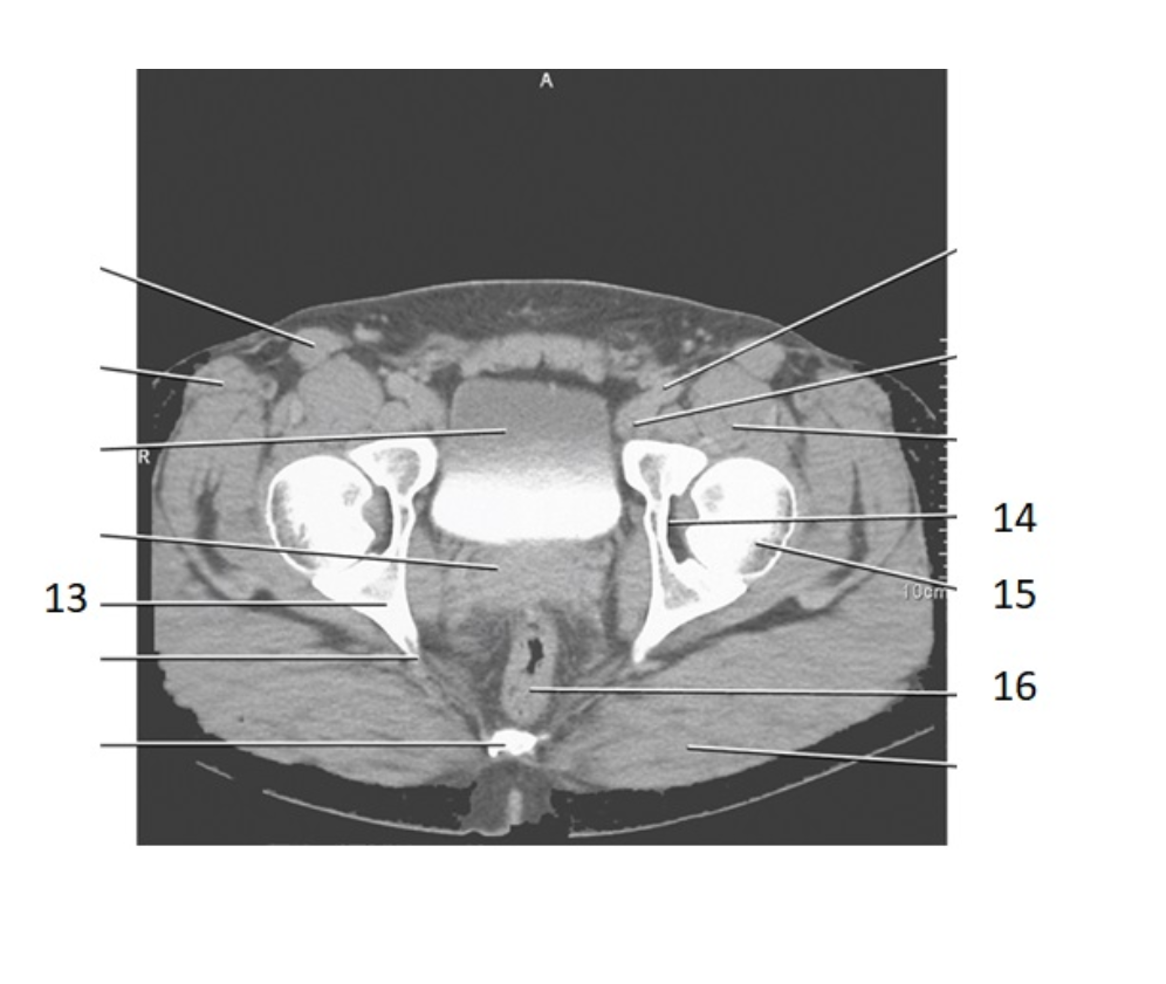

29

pubis

30

ishium

6

ilium

2

sacral prominatory

rectum

14

acetabulum

28

bladder